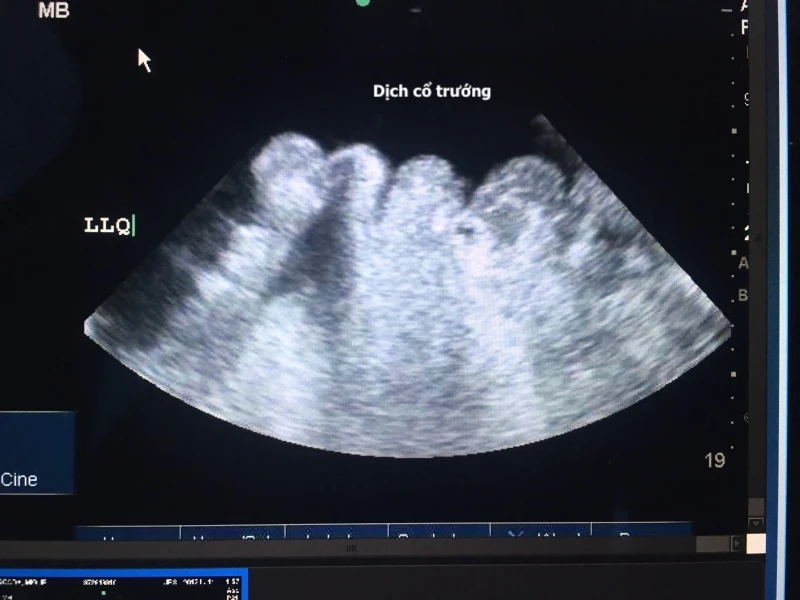

Cổ trướng một tình trạng khiến bụng bệnh nhân phình to do chứa quá nhiều dịch trong khoang bụng (còn được gọi là hiện tượng tràn dịch màng bụng). Hiện cổ trướng nhiều nguyên nhân khác nhau gây ra.

Các nguyên nhân gây ra cổ trướng thường là các bệnh nghiêm trọng. Phương pháp chẩn đoán đầu tiên thường là khám lâm sàng, hình dáng của bụng lúc bệnh nhân nằm và khi đứng lên thường sẽ cho biết có hay không có sự tích tụ của dịch báng.

Để chẩn đoán và xác định tình trạng cổ trướng, bác sĩ sẽ kiểm tra và đánh giá tình trạng sưng ở bụng bệnh nhân. Sau đó kết hợp với chẩn đoán hình ảnh và một số phương pháp xét nghiệm khác để tìm dịch, bao gồm:

- Siêu âm